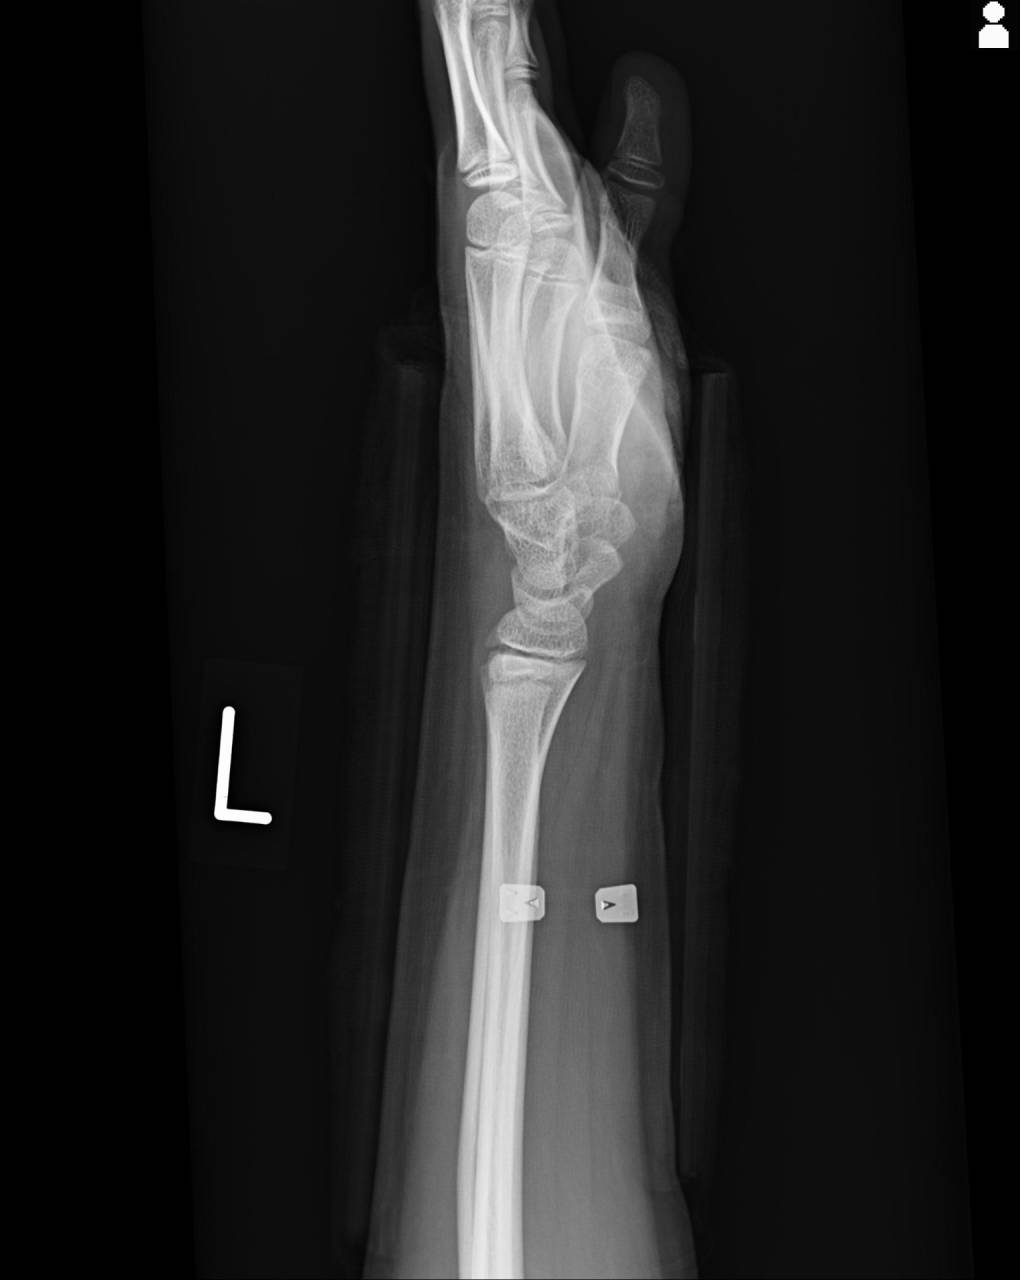

撮影した画像を確認すると、橈骨下端骨折(コーレス骨折)と尺骨茎状突起骨折が確認できました。

尺骨の茎状突起にも骨折の疑いがあったので当整骨院が提携している病院にてレントゲン検査を依頼しました。

実際に超音波観察装置(エコー)にて確認を行っていくと、橈骨下端に骨折線が確認でき、折れ口が完全にズレて噛みこんだ状態ではわずかにズレていると考えました。

ここまでの検査の内容と本人の痛みの感覚をトータルで考察した時に、橈骨下端は折れている俺口が短縮して噛みこんだ状態のため検査と痛みにギャップが生じていると考えました。

実際に圧痛を確認していくと、橈骨下端、尺骨の茎状突起に圧痛があり、ピンポイントで押すとかなり痛がります。